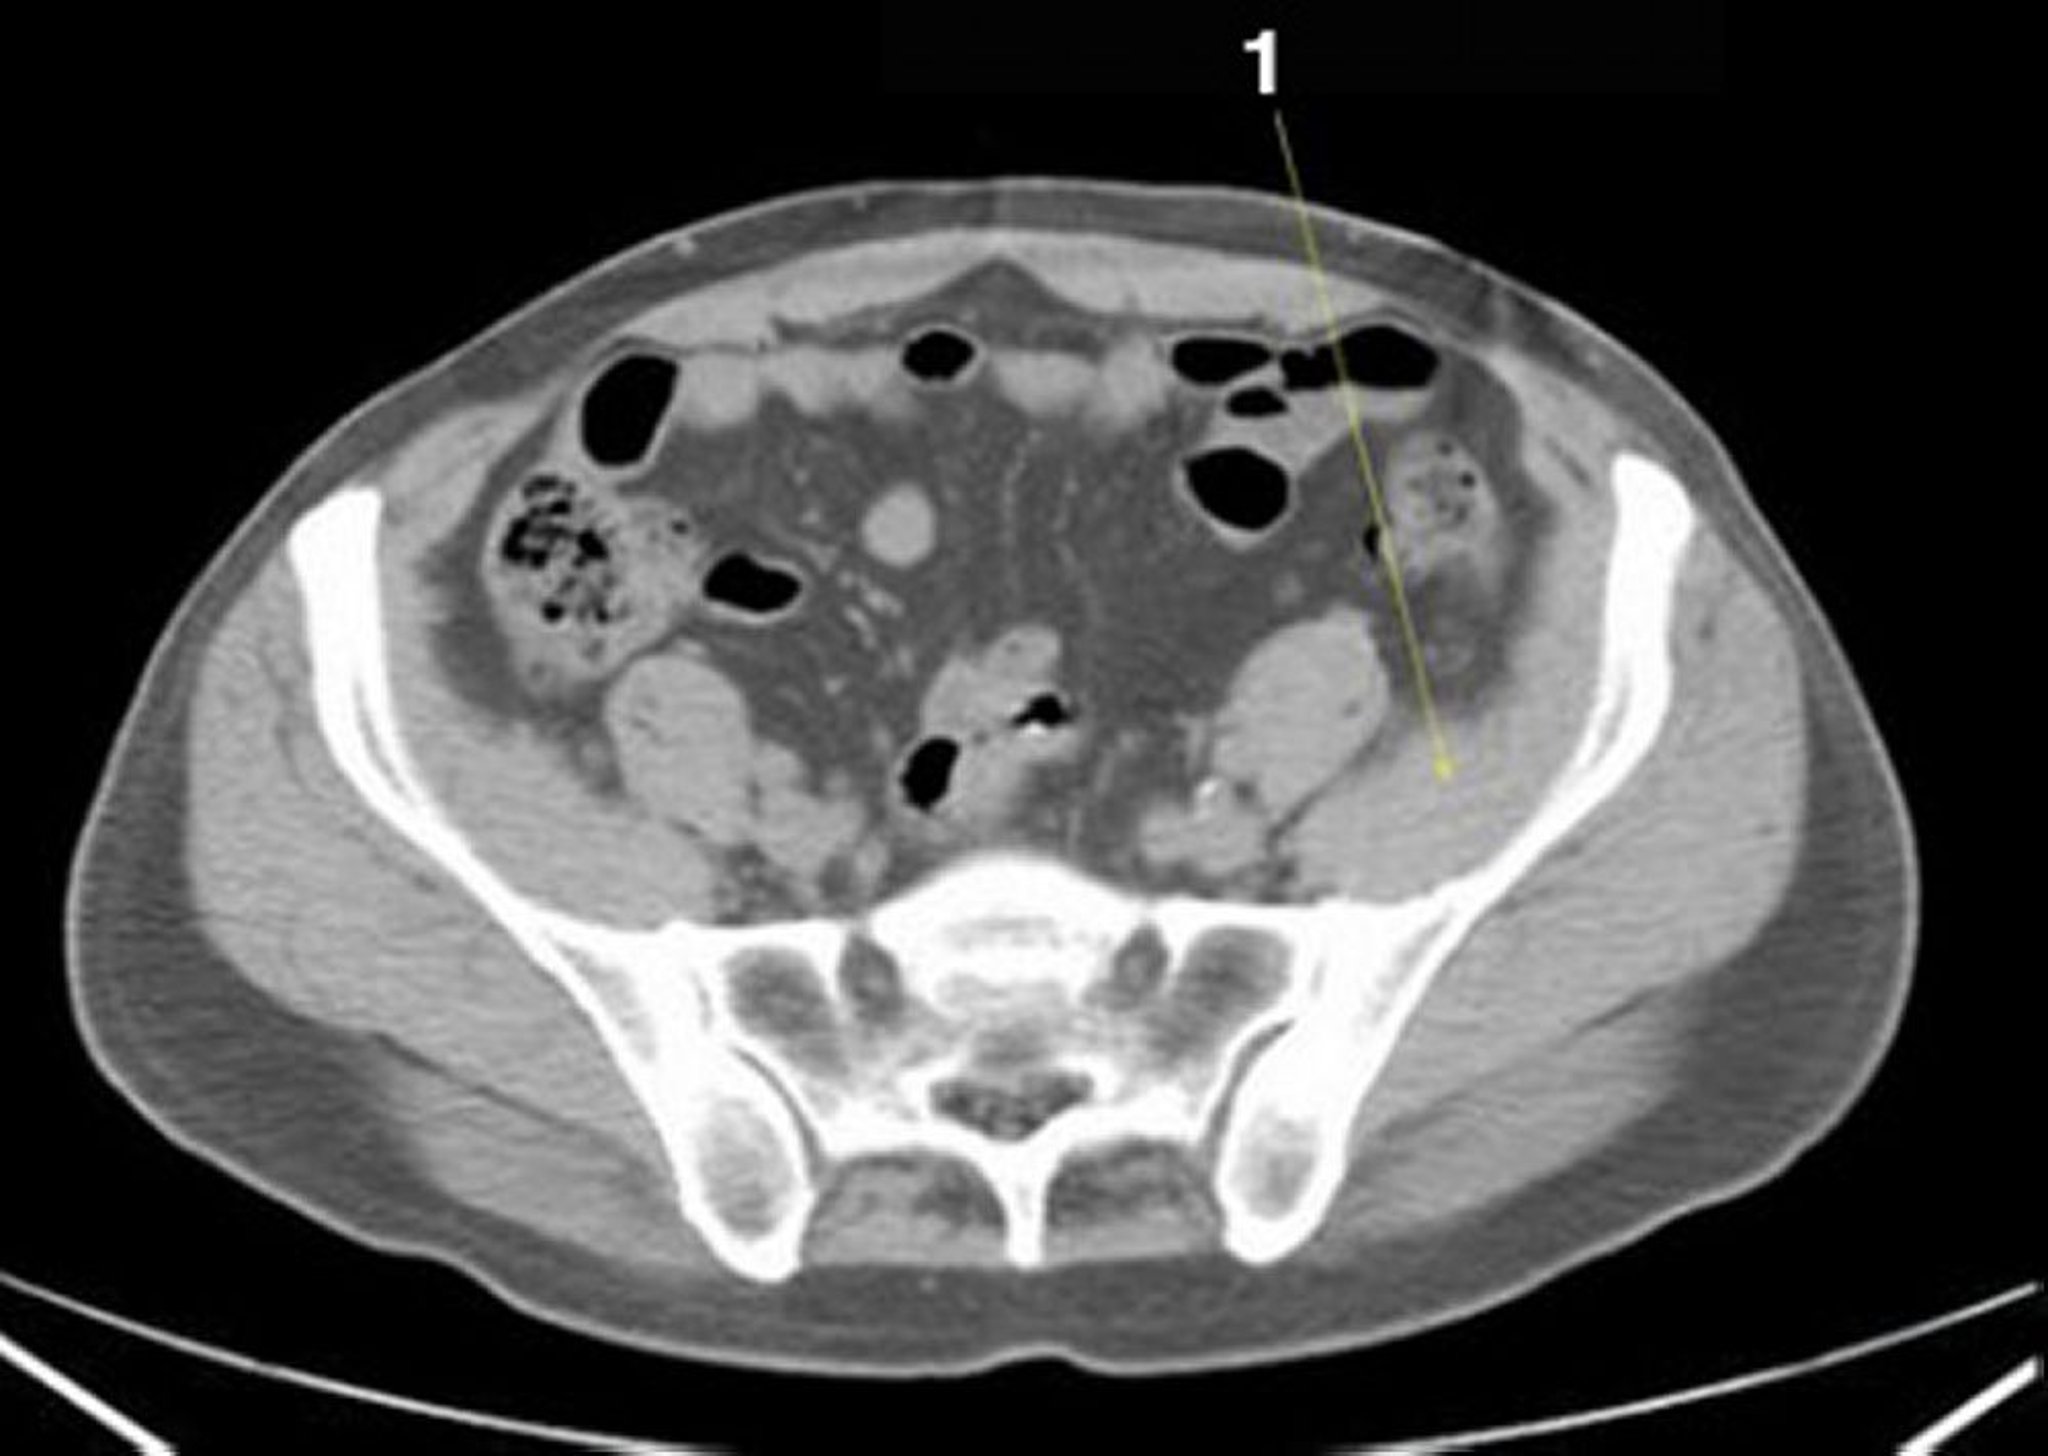

TDM sans contraste de l'abdomen et du bassin montrant une anatomie normale (diapositive 22)

1 = muscle iliaque.